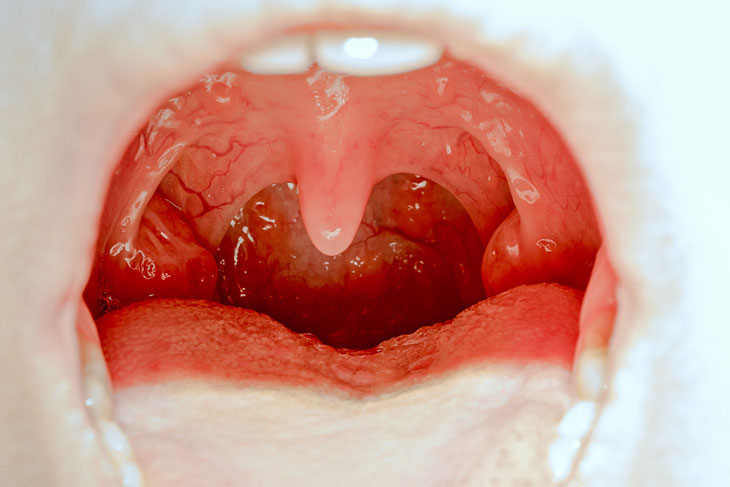

Viêm amidan

Với vai trò quan trọng trong việc giúp cơ thể sản sinh ra kháng thể chống lại sự xâm nhập của virus, vi khuẩn gây bệnh nên amidan có thể bị viêm khi có quá nhiều vi khuẩn, virus xâm nhập. Mọi lứa tuổi đều có thể bị viêm amidan nhưng trẻ em, thanh thiếu niên là đối tượng dễ bị viêm amidan nhất.

Các triệu chứng khởi phát ở giai đoạn cấp tính viêm amidan sẽ là đau họng, sốt, chảy nước mũi, hai bên amidan sưng lớn, vùng họng viêm đỏ… triệu chứng sẽ càng nặng thêm khi bệnh chuyển qua giai đoạn mạn tính.

Viêm amidan do virus, vi khuẩn xâm nhập

Viêm amidan mạn tính sẽ gây nên những triệu chứng như đau nhói vùng họng, thỉnh thoảng ho khan, khàn tiếng, hơi thở hôi… Khi amidan tái đi tái lại nhiều lần trong năm sẽ sưng to cản trở đường ăn uống, gây khó thở và gây nên nhiều biến chứng nguy hiểm khác, giải pháp cuối cùng sẽ phải phẫu thuật cắt bỏ amidan.